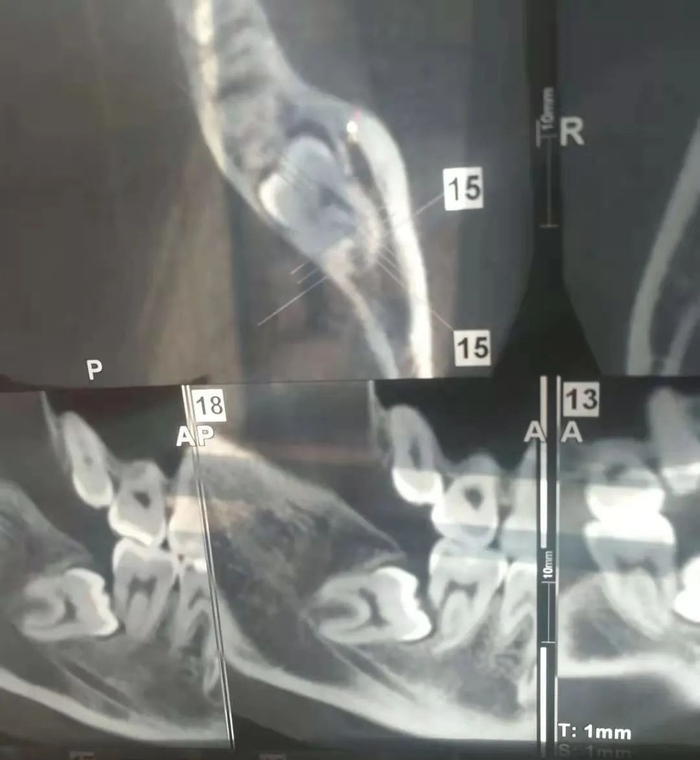

医生指着X光片告诉我,造成牙疼的罪魁祸首并不是第七恒牙,而是我“期盼”了很多年的下智齿。我的下智齿一直暗自生长但完全处在“横生”的状态,且上面覆盖的骨头非常厚。最要命的是,它们分别向着两侧的第七恒牙直挺挺地冲了过去,左侧恒牙的一部分牙根已经被吸收了。这种复杂的情况让小小的私立诊所无法处理,医生特意强调让我一定尽快去口腔专科医院拔除。

年前的号非常不好约,我再约到某知名口腔医院的号已经是好几天后了。当时我做好了拔牙的准备,前一天晚上大吃了一顿。第二天拔牙时,医生看到X光片觉得情况比较复杂,让我先做牙CT检查明确一下具体情况。

我将片子给医生,下定决心躺到牙医椅上准备“任人宰割”,医生仔细端详了许久,和助手小声讨论了几句,却拿着片子走了。我看到他去和别的医生商量了一会儿,最后摇着头来找我:“你这个智齿埋得太深了,上面的骨头太厚,而且你看,这牙根被吸收了这么多,应该保不住了。我们这边门诊做不了,你得挂个专家号去试试。”

随着医生手指噼啪一通操作,我又被第二家医院“扫地出门”。带着片子走在北京隆冬的街上,我感觉自己因为这两颗牙,变成了什么“疑难杂症”患者,唉……拔个智齿好难! 触目惊心的牙CT结果丨作者供图